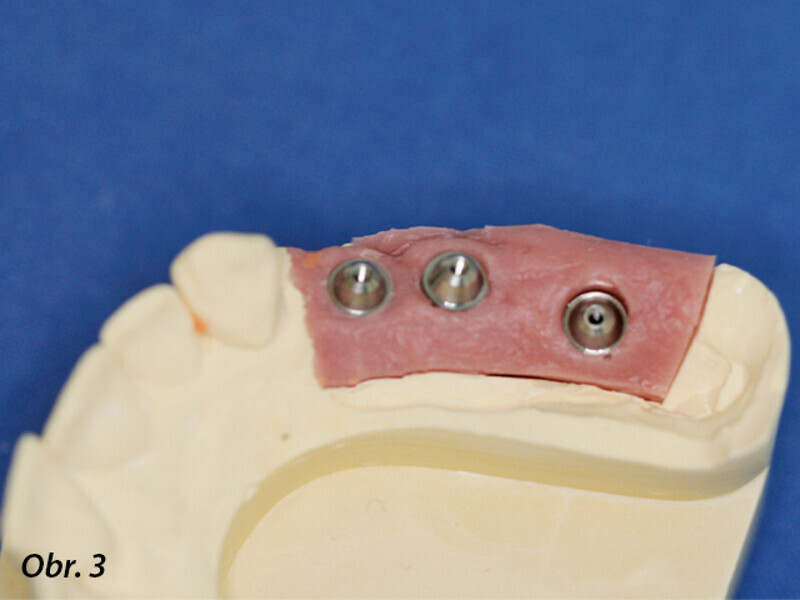

Rehabilitace unilaterální maxilární bezzubosti